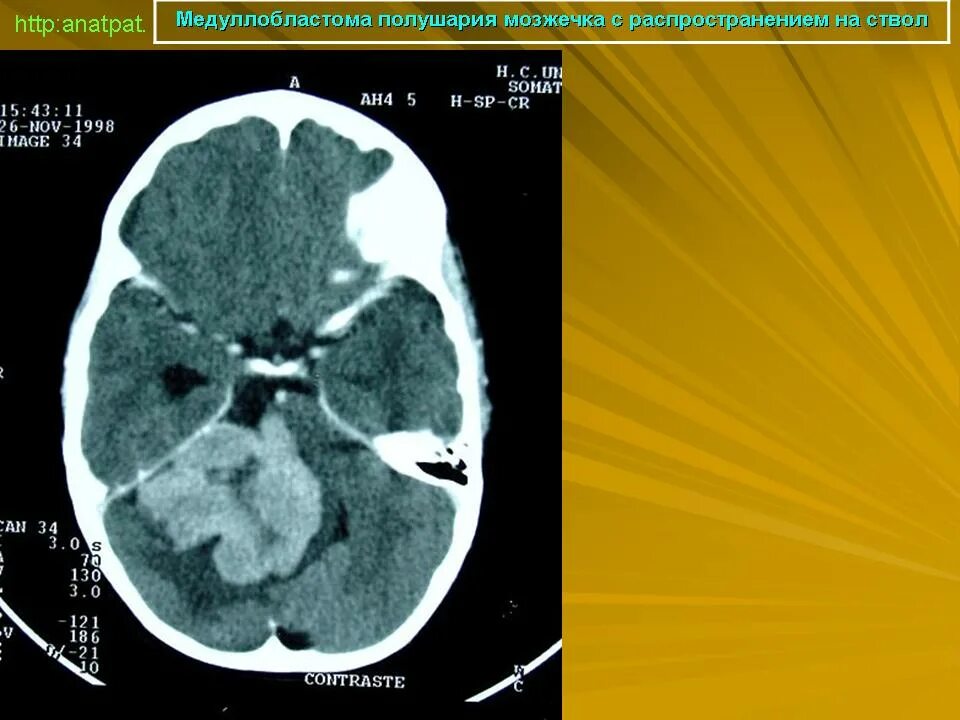

Медуллобластома это